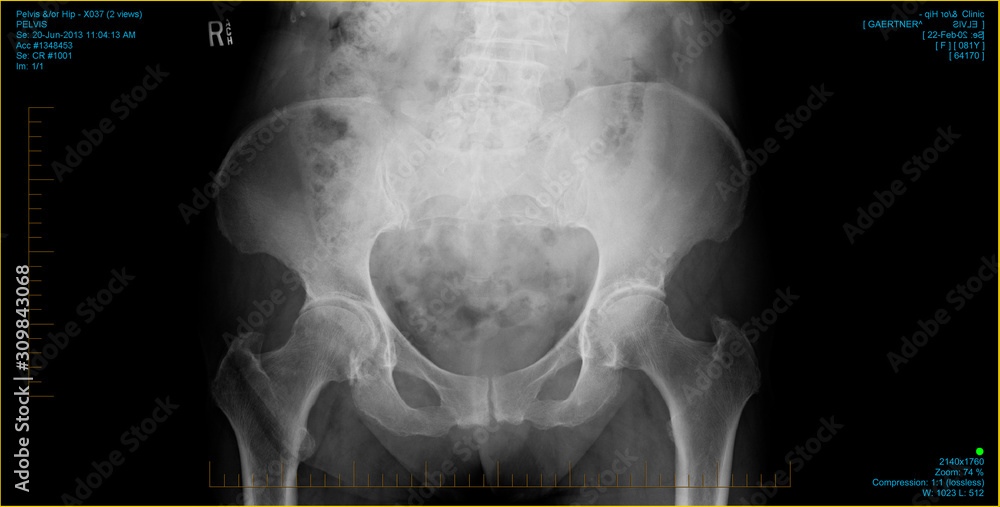

X Rays Of Hip Needing Replacement . How do you know if hip replacement is the right option for you? This artificial joint (prosthesis) helps reduce pain and improve function. Also called total hip arthroplasty, hip replacement. Based on these images and your experiences with hip preservation techniques, we can help you decide whether hip replacement surgery is right for you. Let’s take a look at eight signs that will help you decide if you need hip. Additional signs of trouble include leg length discrepancy, where one leg starts to become shorter than the other, as well as a tendency to walk with your feet pointed outwards. Aspiration of the hip is the best test for excluding infection. 8 signs to know if you need a hip replacement.

8 signs to know if you need a hip replacement. Let’s take a look at eight signs that will help you decide if you need hip. Based on these images and your experiences with hip preservation techniques, we can help you decide whether hip replacement surgery is right for you. Also called total hip arthroplasty, hip replacement. Additional signs of trouble include leg length discrepancy, where one leg starts to become shorter than the other, as well as a tendency to walk with your feet pointed outwards. Aspiration of the hip is the best test for excluding infection. This artificial joint (prosthesis) helps reduce pain and improve function. How do you know if hip replacement is the right option for you?